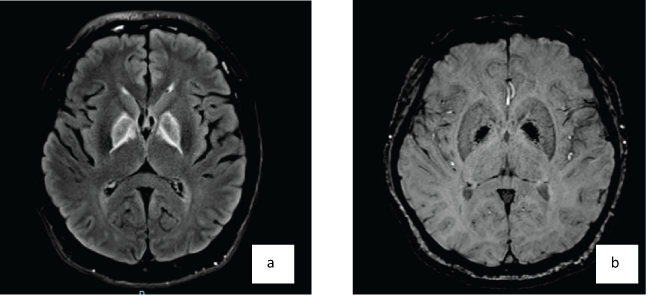

A 41-year-old gentleman attempted suicide by burning charcoal in an enclosed room. He was found unconscious and was intubated for poor Glasgow Coma Scale (GCS). He was successfully extubated and transferred to our hospital on day 6. Initial physical examination showed no neurological deficits with normal scoring of Mini-Mental State Examination (MMSE) and Montreal Cognitive Assessment (MOCA). Computerized Tomography (CT scan) of the brain was done on day 8 (Figure 1). Magnetic Resonance Imaging (MRI) of brain done on day 10 was shown in Figure 2A and Figure 2B. He had major depression and was transferred to the care of psychiatrist. Initial neuropsychological assessment showed subtle deficits in learning, retrieval of information and verbal fluency.

Figure 2: MRI brain done on day 10. A,B) High FLAIR signal with hyperintense rim in the bilateral globus pallidus with susceptibility.